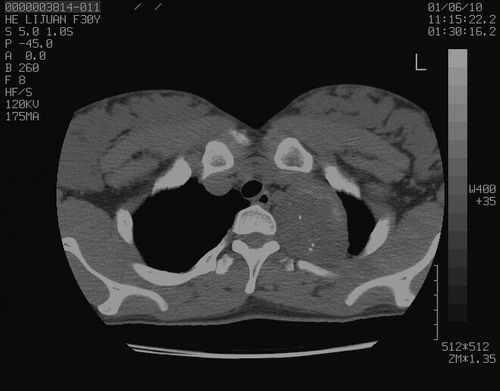

怀孕3个月时(2009-3至4月间),自述突感左侧前后胸疼痛1天,以前胸明显,随后偶感闷痛,余未见异

左肺尖脊柱旁沟肿块,境界清楚,边缘光滑,密度不均,内有多发点片状钙化,考虑良性肿瘤,骨软骨瘤或神经源性肿瘤可能,肺错构瘤不除外。

左后上纵隔见一类圆形肿块影,外侧边界清,密度不均匀,内可见点状钙化影,增强呈不均匀强化,考虑神经源性肿瘤可能。期待病理结果。